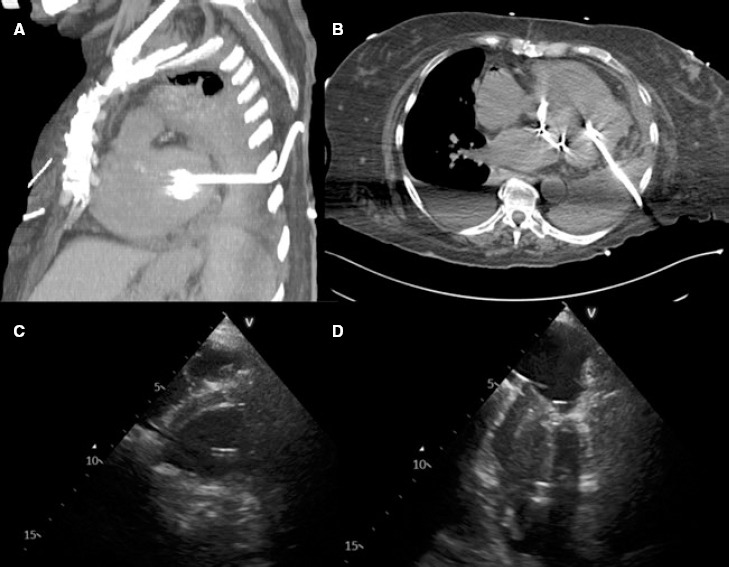

Percutaneous closure of left ventricular puncture after thoracentesis.